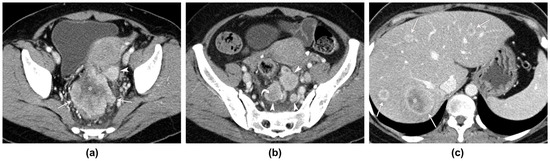

| Age (y)/ Sex | Clinical Presentation | Radiologic Studies | Tumor Location | Morphologic Type | Maximum Wall Thickness (mm) | Enhancement Pattern of the Tumor * | Enhancement Degree † | Tumor Necrosis | LAP (Number/Diameter (mm)) ‡ | LAP Necrosis | Adjacent Organ Invasion | Distant Metastases |

|---|---|---|---|---|---|---|---|---|---|---|---|---|

| 70/F | Abdominal pain | CT, US | Sigmoid colon | Bulky mass | 44 | Heterogeneous | Well (3.01) | Yes | 0/NA | NA | Right ureter and ovary, ileum, urinary bladder, iliopsoas muscle, and uterus | No |

| 59/M | Hematochezia | CT, PET-CT | Rb | Circumferential wall thickening | 24 | Homogeneous | Moderate (1.22) | No | 10/21 | Yes | Levator ani muscle, prostate, urinary bladder | No |

| 67/F | Hematochezia | CT | Ra | Eccentric wall thickening | 14 | Homogeneous | Moderate (1.36) | Yes | 2/12 | Yes | No | No |

| 92/M | Hematochezia, constipation | CT | Rb | Bulky mass | 44 | Heterogeneous | Well (1.53) | Yes | 2/17 | Yes | Prostate | No |

| 54/F | Fever | CT, US, PET-CT | Ra | Bulky mass | 49 | Heterogeneous | Well (2.02) | Yes | 8/21 | Yes | Uterus | Liver |

| 86/M | Hematochezia | CT | Rb | Circumferential wall thickening | 25 | Homogeneous | Well (2.36) | No | 1/25 | Yes | Levator ani muscle | No |

| 76/M | Abdominal pain | CT | Ra | Circumferential wall thickening | 14 | Homogeneous | Moderate (1.23) | No | 1/8 | No | No | No |

| 54/F | Hematochezia | CT | Rb | Circumferential wall thickening | 19 | Homogeneous | Moderate (1.16) | Yes | 1/12 | Yes | No | No |